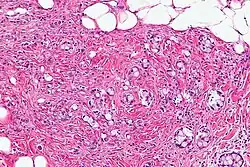

| Micrograph showing a goblet cell carcinoid. H&E stain. | |

GCCs are diagnosed by pathology. They have a characteristic biphasic appearance which includes (1) goblet cell-like cells, and (2) neuroendocrine-type nuclear chromatin (stippled chromatin).